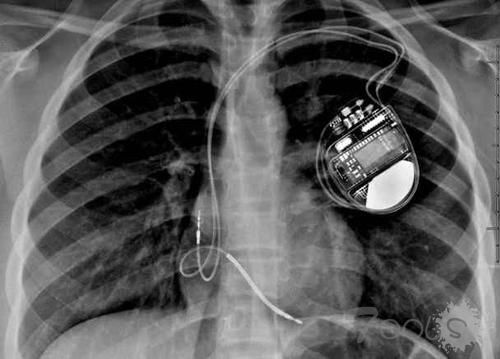

他才是真正的“黑客”?不仅破解ATM无限吐钱、还能入侵心脏起搏器!

随着时代的变迁,科技发展越来越迅速,并且逐渐进入了智能化科技时代。然后,操控这些高端技术的人才大有人在,如果是对社会做出有益处的事,那么这些人将会成为国家的栋梁之才;但是如果这些人抱有居心叵测的思想观念,那么他可能会对社会以及国家造成一定的影响,而这种人就被成为黑客。在大家的印象